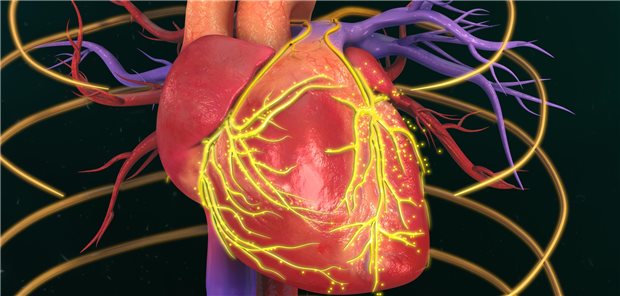

Das Herzpflaster wird für die Operation vorbereitet.

© UKSH

Schwere Herzinsuffizienz

Herzpflaster baut Herzmuskulatur auf